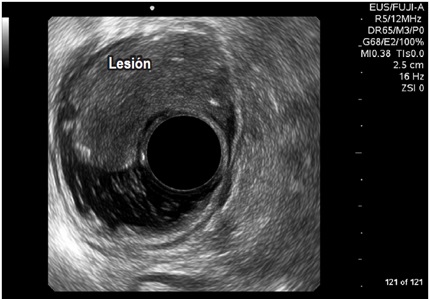

Por otro lado, en el grupo masculino con estudio por incontinencia, el diagnóstico en todos fue cambios por atrofia del aparato esfinteriano, que pudo verse en cualquiera de las localizaciones del canal anal y que se evidenció como engrosamiento de los músculos en general y cambios difusos de la ecogenicidad de los mismos, sin posibilidad de determinar el borde que los delimita. Se encontró fístula perianal en 16 pacientes (11,8%); la principal forma de presentación de las fístulas fue transesfintérica (37,5%), seguida por las interesfintéricas y anovaginales (figuras 3 y 4). Doce pacientes presentaron absceso perianal (8,8%); de estos, el 83% correspondió a abscesos submucosos o isquiorrectales (figura 5).

Los demás diagnósticos finales se presentan en la tabla 4. Es de resaltar que se pudo determinar en el grupo diagnosticado como neoplasia benigna de recto, la posibilidad de resección endoscópica en lesiones que tenían planeadas cirugías más invasivas (figura 6 y 7), así como la posibilidad de determinar la recuperación del aparato esfinteriano en 3 pacientes en seguimiento por cáncer de canal anal después de manejo por parte de oncología. En 2 pacientes de los diagnosticados con neoplasia maligna de recto se identificó lesión menor a T2 y N0 según las clasificación de TNM (figura 8), considerándose lesiones tempranas; en el otro 88,8% se encontraron lesiones avanzadas (figura 9 y 10). También se anota que, dentro de la categoría otros, están con orden de frecuencia de mayor a menor endometriosis o endometrioma, enterocele, fisura anal, várices rectales y un caso de cáncer de colon sigmoides.